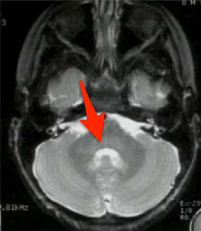

What structure is indicated in the T2 image below?

Middle cerebellar peduncles. Note that most of the white matter (which is dark on FLAIR) from the MCP makes up the core of the cerebellum.